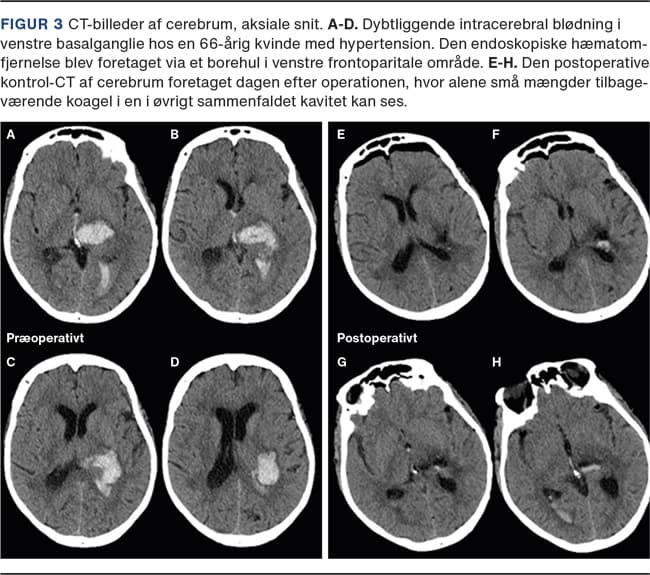

I Figur 2 og Figur 3 vises to sygehistorier med dybtliggende ICH i basalganglier, hvor begge er fjernet med endoskopisk operationsteknik. Begge patienter har haft et kort (24 timers) forløb i et neurointensivt afsnit, hvorefter neurorehabilitering kunne påbegyndes.